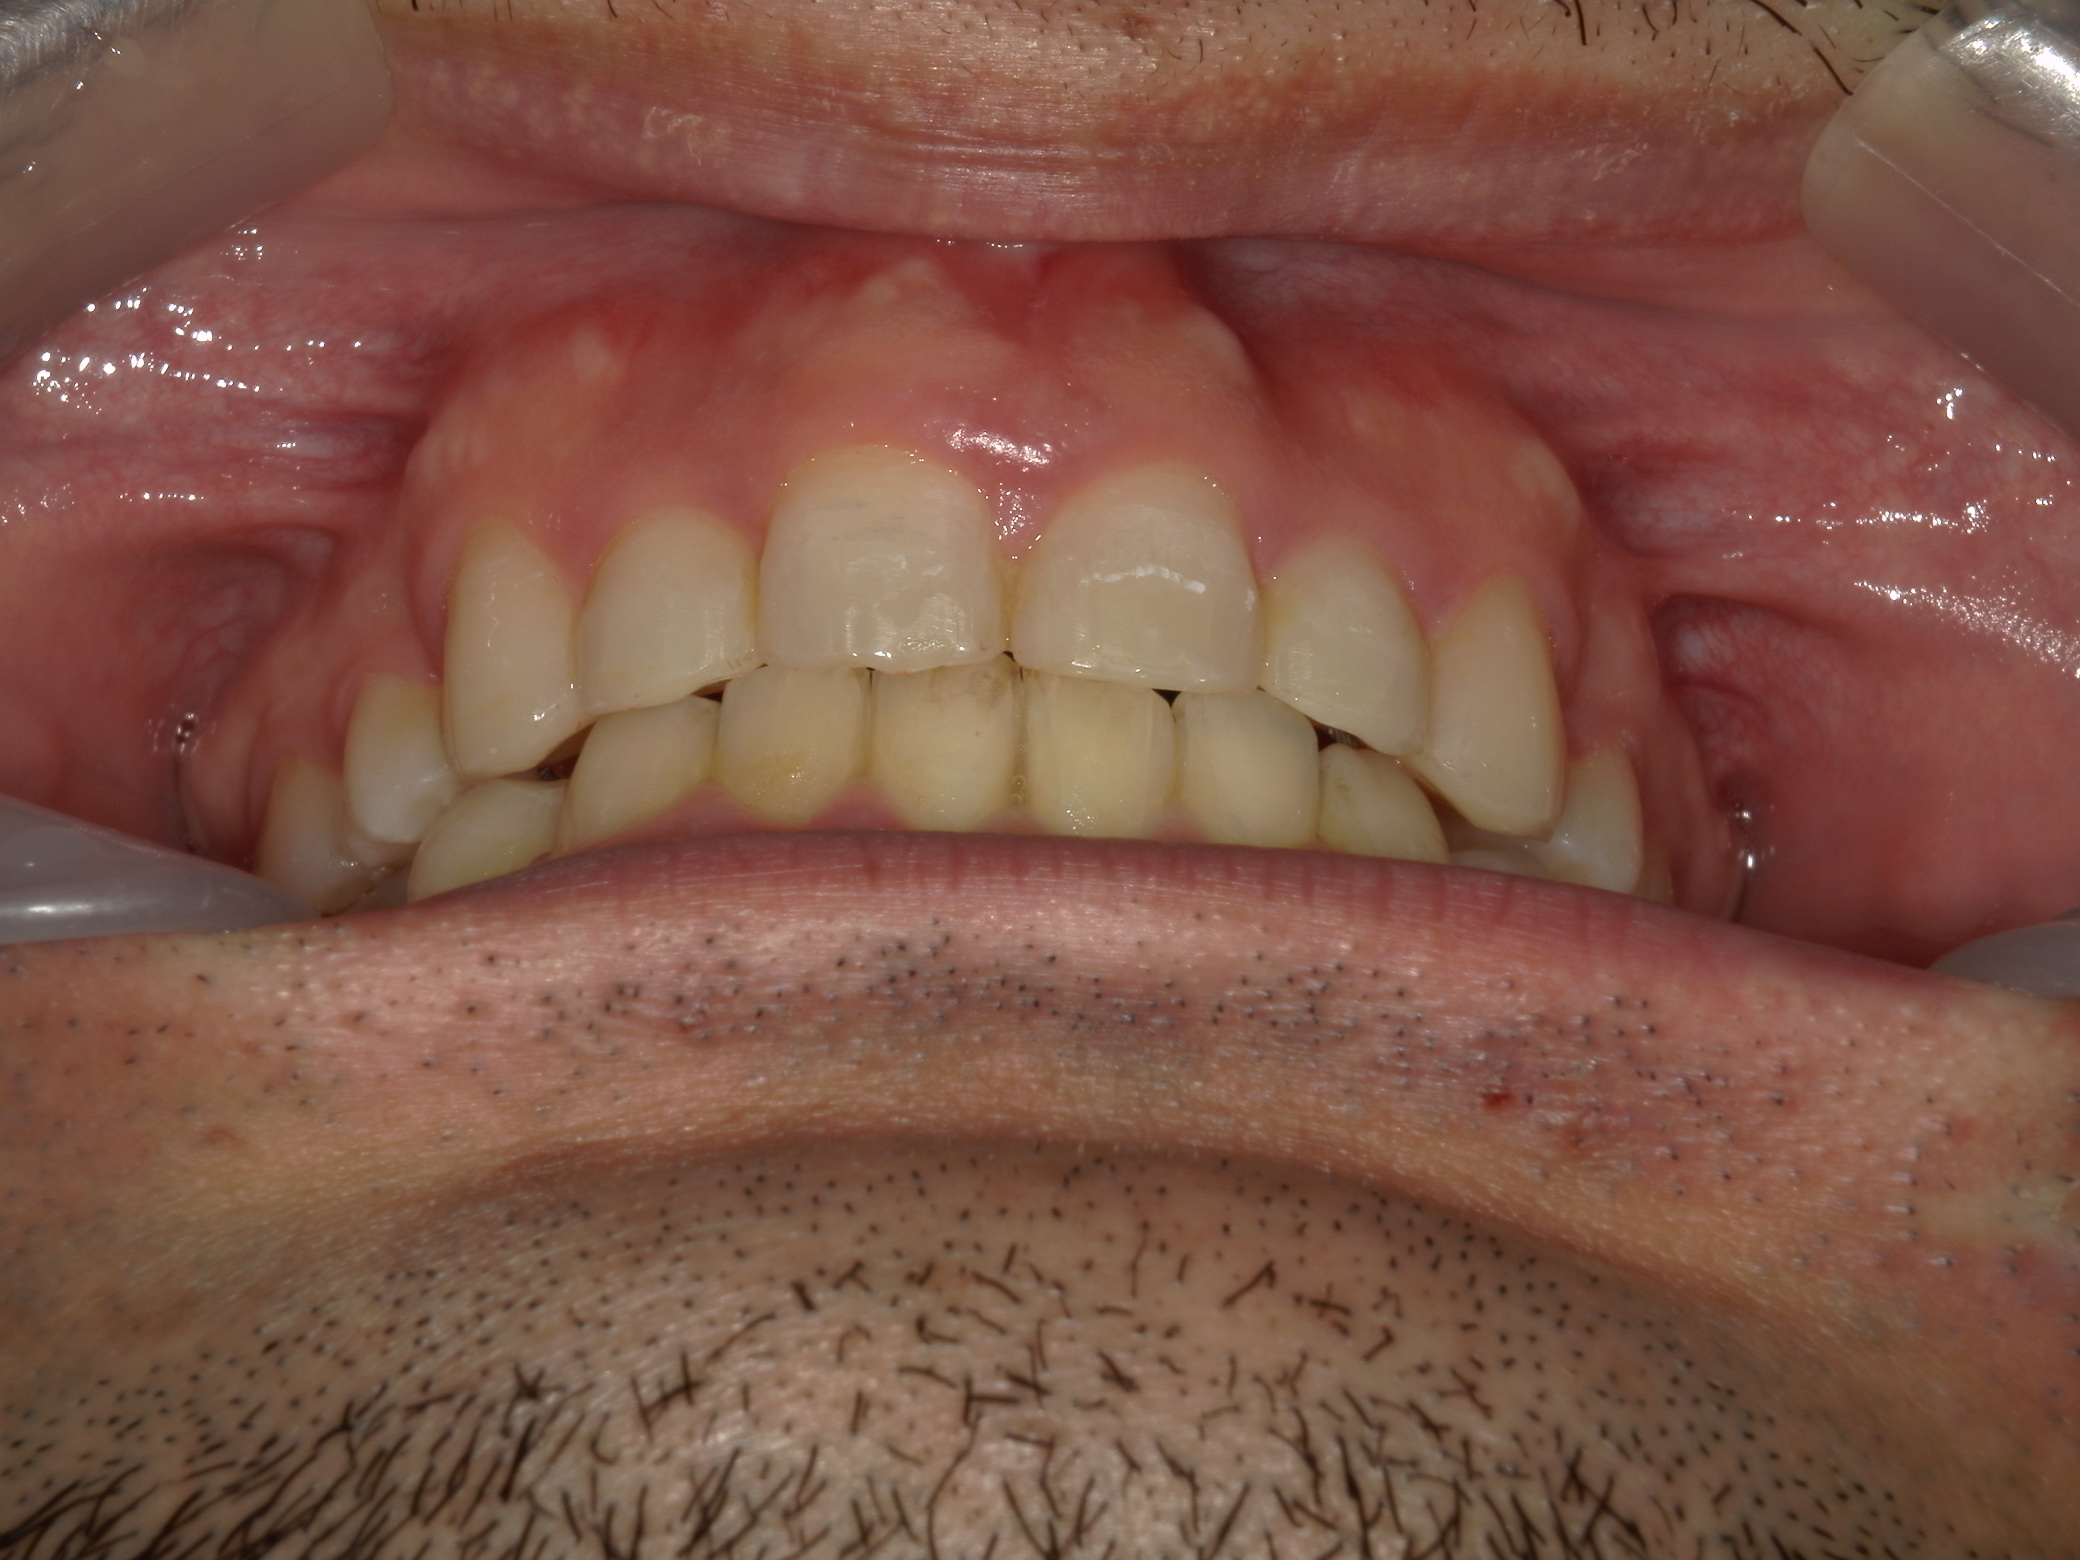

全顎ワイヤー矯正 症例(79)

主訴: 前歯が噛み合わない。歯並びが気になる。

カテゴリー : ガタガタ(叢生) , 噛み合わせが深い(過蓋咬合)